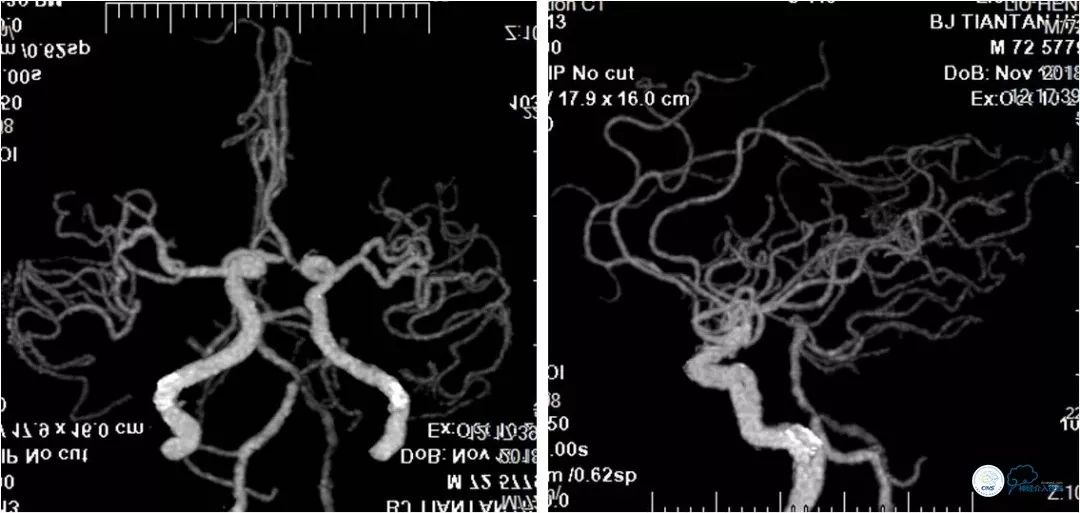

患者,男,72岁。主因“反复头晕3年”入院。患者3年前突发短暂头晕,无其他伴随症状,就诊于当地医院,行CTA提示:双椎动脉V4段-基底动脉交界区狭窄。3年来症状反复发作,多次行颅内动脉血管成像,显示病变程度逐渐加重(图1)。

图1

头部CTA:双椎动脉-基底动脉交界区重度狭窄(图3)。

图3